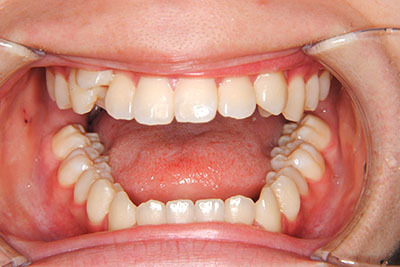

歯が乳歯から永久歯に生え変わった小学生高学年や、中高生でも矯正治療に手遅れということは全くありません。

成長中の顎の骨を矯正できたり、この時期の矯正はおとなになってから矯正治療を始めるよりも短期間で済むことがほとんどです。当院だとおおよそ1年で動的治療(マルチブラケット装置をつける期間)が終わることが多いです。